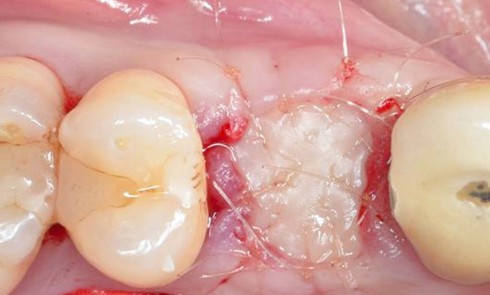

En mars 2016, la patiente se plaint d’une sensibilité sur la 25 et on note cliniquement une inflammation gingivale associée à un décalage apical du rebord marginal et de la ligne muco-gingivale en comparaison de leur situation visualisée au niveau des coiffes supra-implantaires. La couronne clinique est réduite et une infraposition avec une inocclusion d’environ 2 mm par rapport au plan d’occlusion et aux dents antagonistes est également notée (fig. 2 à 4). Un saignement au sondage ainsi qu’une poche de 5 mm en distal sont constatés. Le test de percussion est positif. Les tissus péri-implantaires adjacents ne présentent aucun signe de mucosite.

La radiographie péri-apicale au long cône confirme, sur la 25, un élargissement desmodontal, notamment en distal, des niveaux osseux mésio-distaux réduits par rapport aux clichés de contrôle précédents (les radiographies sont réalisées avec une technique parallèle avec des angulateurs de Rinn non personnalisés), un apex radiculaire normal et des niveaux osseux stables sur les implants adjacents (fig. 5). Le cisaillement systématique du fil dentaire lors de son passage confirme des points de contact très étroits entre 24, 25 et 26.